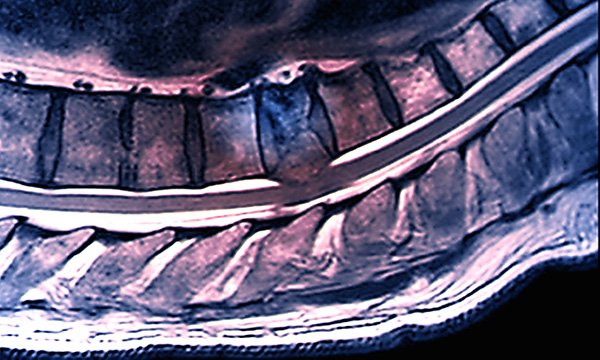

The benefits of providing a palliative care bone metastases review service